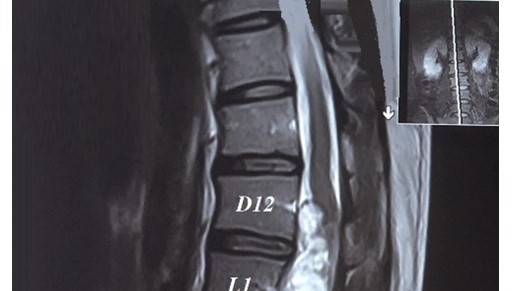

Bí tiểu cấp do chèn ép chùm đuôi ngựa trên bệnh nhân thoát vị đĩa đệm cấp: Báo cáo 2 trường hợp lâm sàng

ThS. Đinh Thị Phương Hoài, ThS. BSCKII. Nguyễn Thanh Minh, ThS. Nguyễn Vĩnh Lạc, BSNT. Trần Thị Mai Diệu, PGS.TS. Nguyễn Khoa Hùng.

U Schwannoma chóp tủy khổng lồ gây yếu liệt hai chi dưới: Báo cáo trường hợp lâm sàng

ThS. Đinh Thị Phương Hoài, ThS. BSCKII Nguyễn Thanh Minh, ThS. Nguyễn Vĩnh Lạc